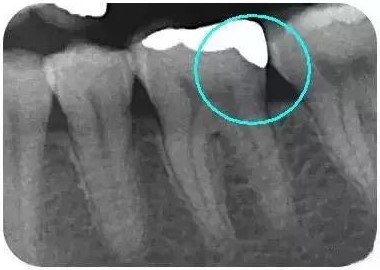

从下面这张X线片中可以看出,嵌体远中边缘没有悬突,与牙体边缘密合相接。